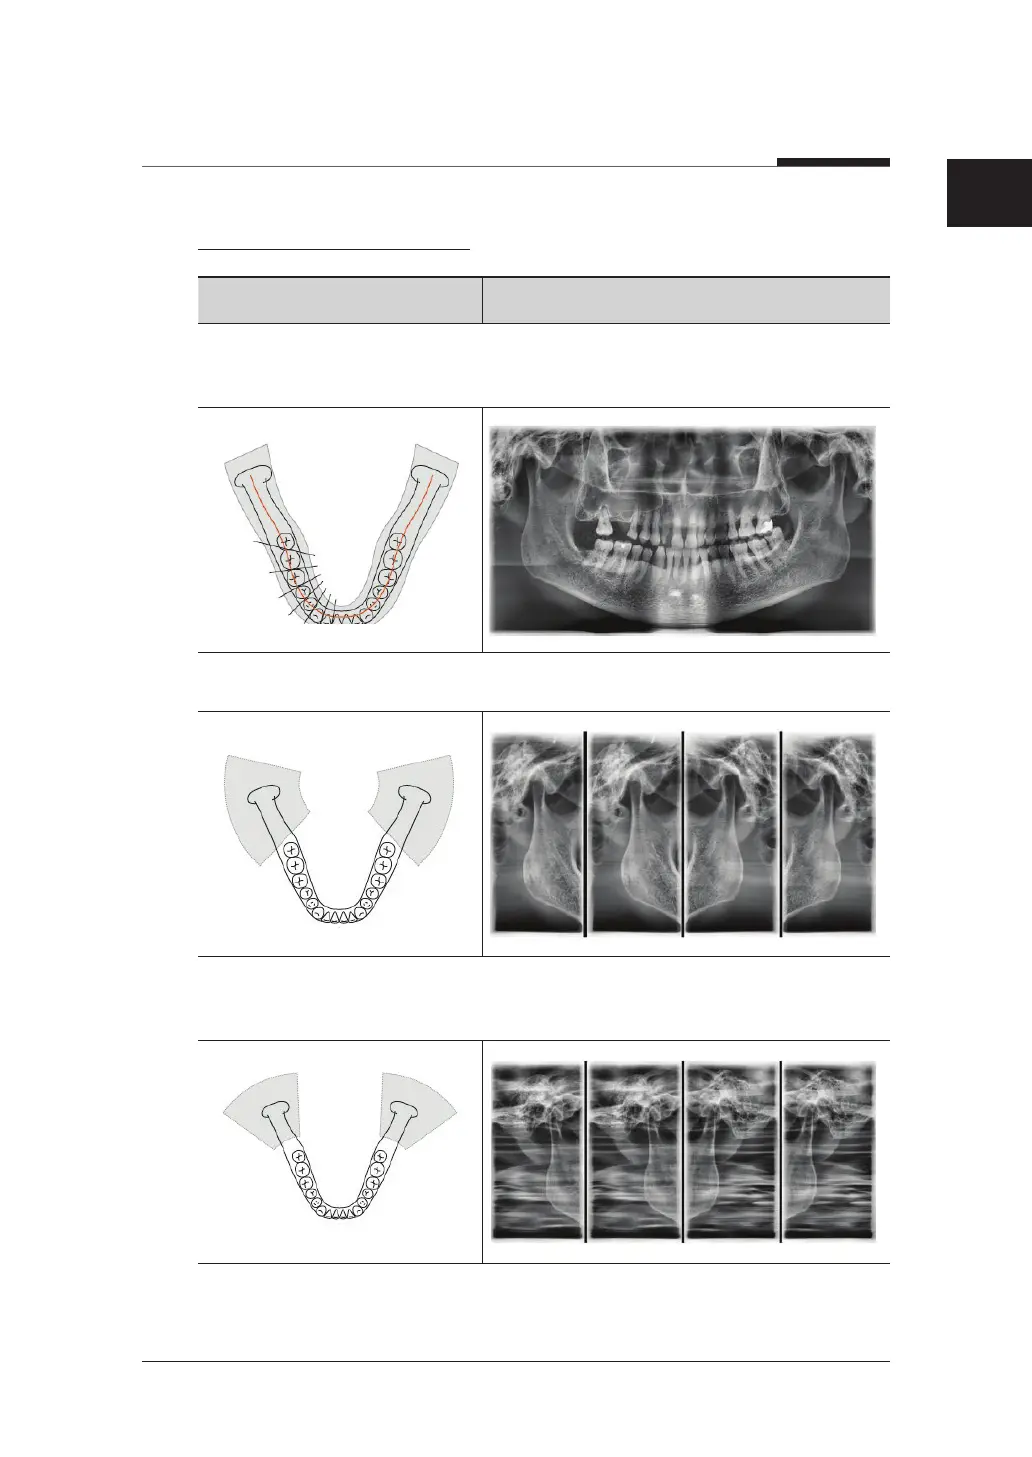

SPECIAL EXAMINATION

Examination Program Image

Orthogonal (Standard): Panoramic image where the x-ray angle enters vertically in

between the teeth so overlapping images are minimized.

TMJ LAT Open / Close: The acquired image focused on the lateral TMJ area.

TMJ PA Open / Close: The acquired image focused on the posterior-anterior TMJ

area.